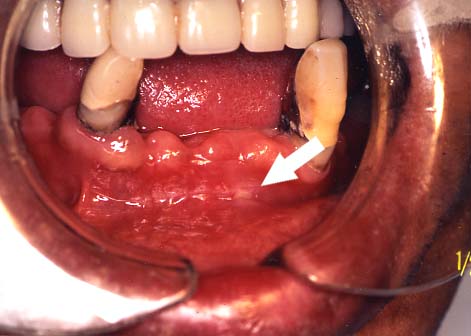

3.レーザー照射後

白濁となり,さわっても痛くなく

食べてもしみません。